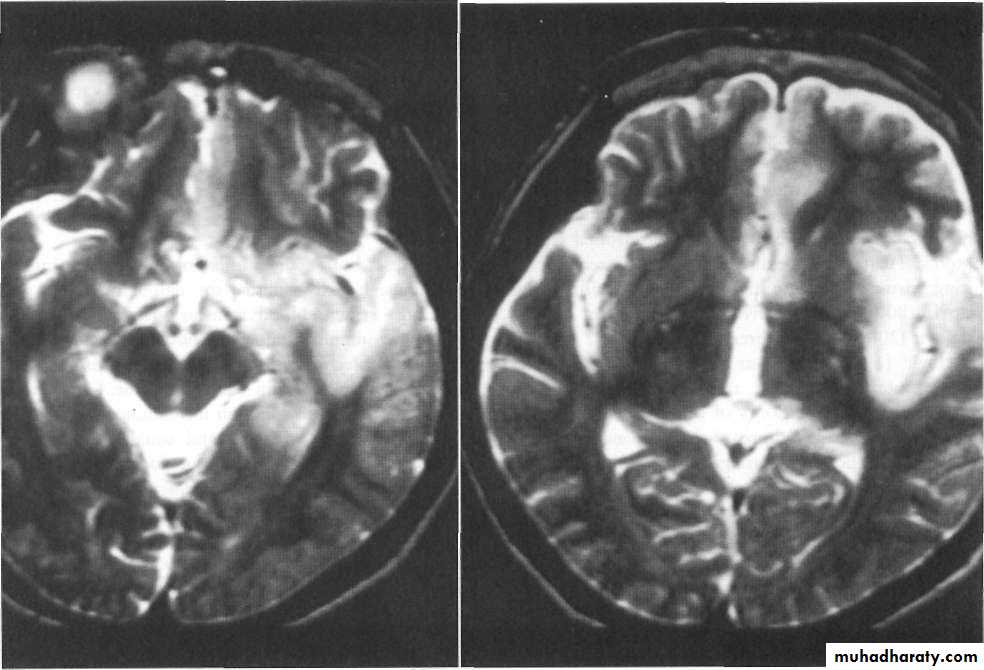

EEG, brain MRI, CSF exam

MRI : temporal lobe

ENCEPHALITIS

Causes severe haemorrhagic encephalitis affecting temporal lobe,

Herpes simplex encephalitis